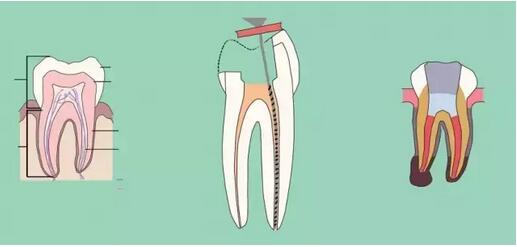

五、根管預(yù)備

根管預(yù)備的方法無(wú)非是采用上面提到的三種(標(biāo)準(zhǔn)法,逐步后退法,冠向深入法)中的哪一種或者或聯(lián)合法,器械常用而推薦的大致有以下的種類:k挫(10#~40#),c挫(6#,8#,10#),G鉆,protaper手用兩套不同器械不同的預(yù)備方法:

①不銹鋼k挫,這套系統(tǒng)常規(guī)使用逐步后退法,預(yù)備的手法使用平衡力法。

②protaper器械使用逐步深入法,根管系統(tǒng)是很復(fù)雜的,任何器械和任何方法的預(yù)備都不能到達(dá)整個(gè)根管系統(tǒng),所以機(jī)械預(yù)備和化學(xué)預(yù)備的結(jié)合非常重要(采用盡量小的針頭,上下移動(dòng)輕壓沖洗,并防止針頭卡住)。

七、根管充填

充填時(shí)機(jī),無(wú)自覺(jué)癥狀,無(wú)明顯叩疼,根管內(nèi)無(wú)異味,無(wú)滲出,無(wú)急性尖周炎癥狀即可充填,不必等到所有癥狀消失,反復(fù)的封藥容易對(duì)尖周造成大大刺激。

充填的質(zhì)控標(biāo)準(zhǔn):

a、充填物距根尖小于等于2mm;

b、充填致密,連續(xù),錐度合適;

c、充填完畢燙牙膠尖根管口下2~3mm,小號(hào)充填器冷加壓;

d、對(duì)于欠充患者需重新預(yù)備充填,而超充原則上不建議重做,隨訪,必要時(shí)根尖手術(shù)治療。目前研究表明,在其他因素相同的前提下,超充的預(yù)后差于欠充。